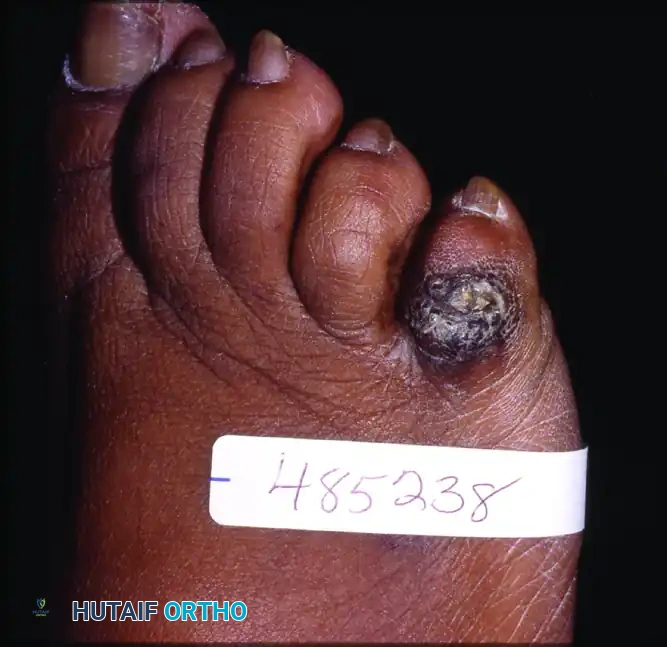

Visible shortening of the hallux, failure of the toe to engage the ground, and lesser toe metatarsalgia or keratosis (callus) indicate mechanical unloading of the first ray.

Examination of the seated patient allows observation for callus, skin irritation, or presence of dorsal or medial bunion.

Skin irritation may be present over the dorsal exostosis or medial bunion.